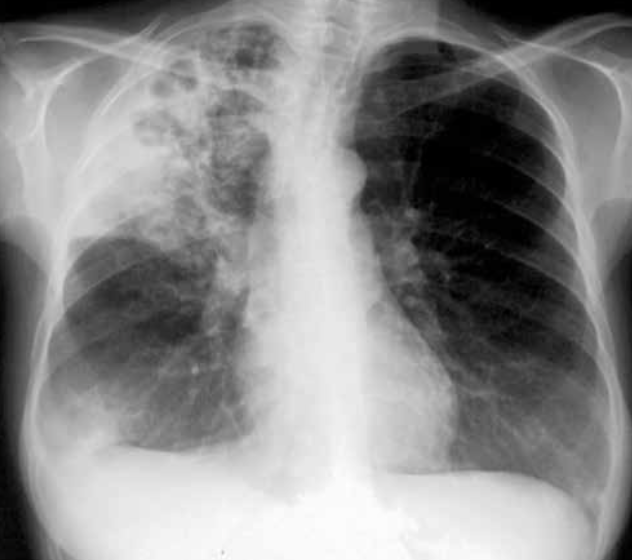

Hemorragia pulmonar bilateral. Aunque la placa de tórax puede resultar útil para el diagnóstico de hemorragia pulmonar, el contexto clínico es fundamental ya que los hallazgos radiológicos son indistinguibles del edema alveolar o de la neumonía. Las radiografías seriadas obtenidas durante varios días tras el episodio de hemorragia pulmonar aguda muestran un cambio de patrón progresivo: los primeros días se observan densidades alveolares difusas con broncograma aéreo de predominio bibasal o perihiliar. La resolución es rápida, mostrando un patrón reticular a los 2 o 3 días que va disminuyendo gradualmente hasta que la radiografía se normaliza por completo en torno a las 2 semanas.